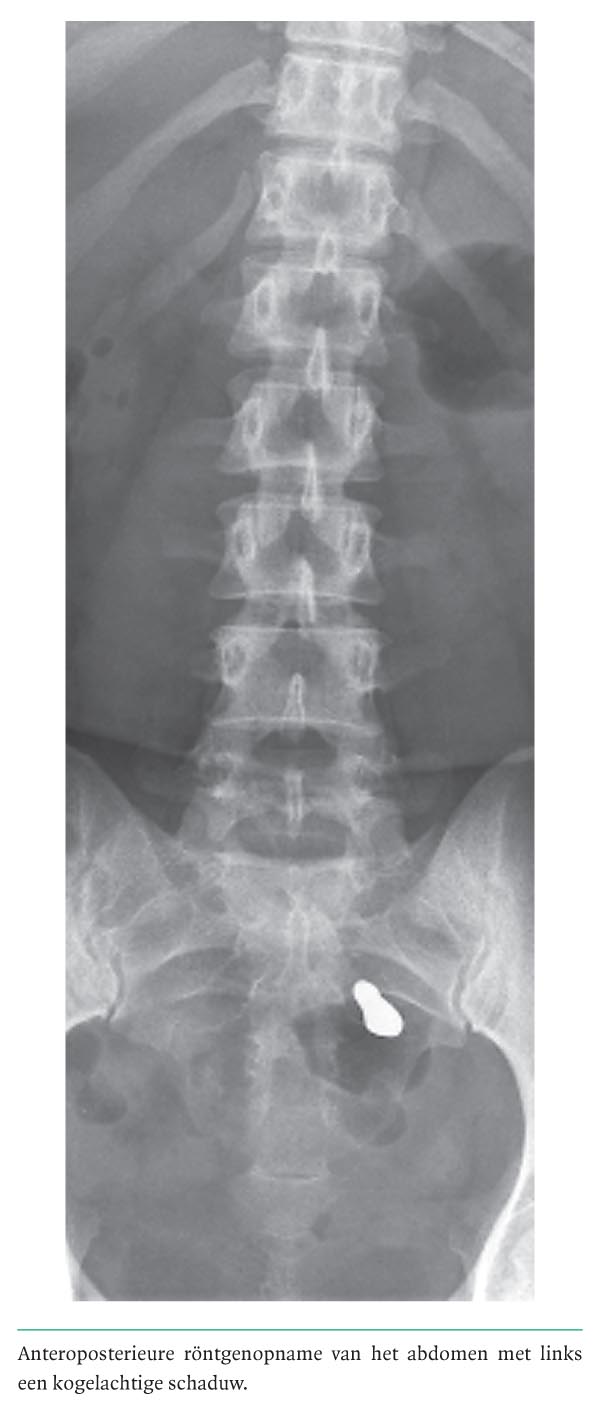

Diagnose in beeld (258). Een vrouw met een 'kogel' in het abdomen

Bij een 48-jarige vrouw werd op een röntgenfoto bij toeval een metaalachtig artefact links ter hoogte van het sacrum gevonden (figuur). De radioloog dacht aan een kogel. Patiënte kon zich echter geen schietincident herinneren. Zij werd naar ons verwezen vanwege een uitgebreide gynaecologische voorgeschiedenis, met de vraag of wij het ‘metaaldeeltje’ konden verklaren. De voorgeschiedenis vermeldde onder andere langdurige subfertiliteit, waarvoor patiënte 17 jaar eerder 2 maal hysterosalpingografie had ondergaan. Zij had geen gynaecologische klachten en wij vonden geen verklaring voor het metaalachtige artefact. Als toevalsbevinding werden echoscopisch links 2 cysten gezien van respectievelijk 4 en 7…